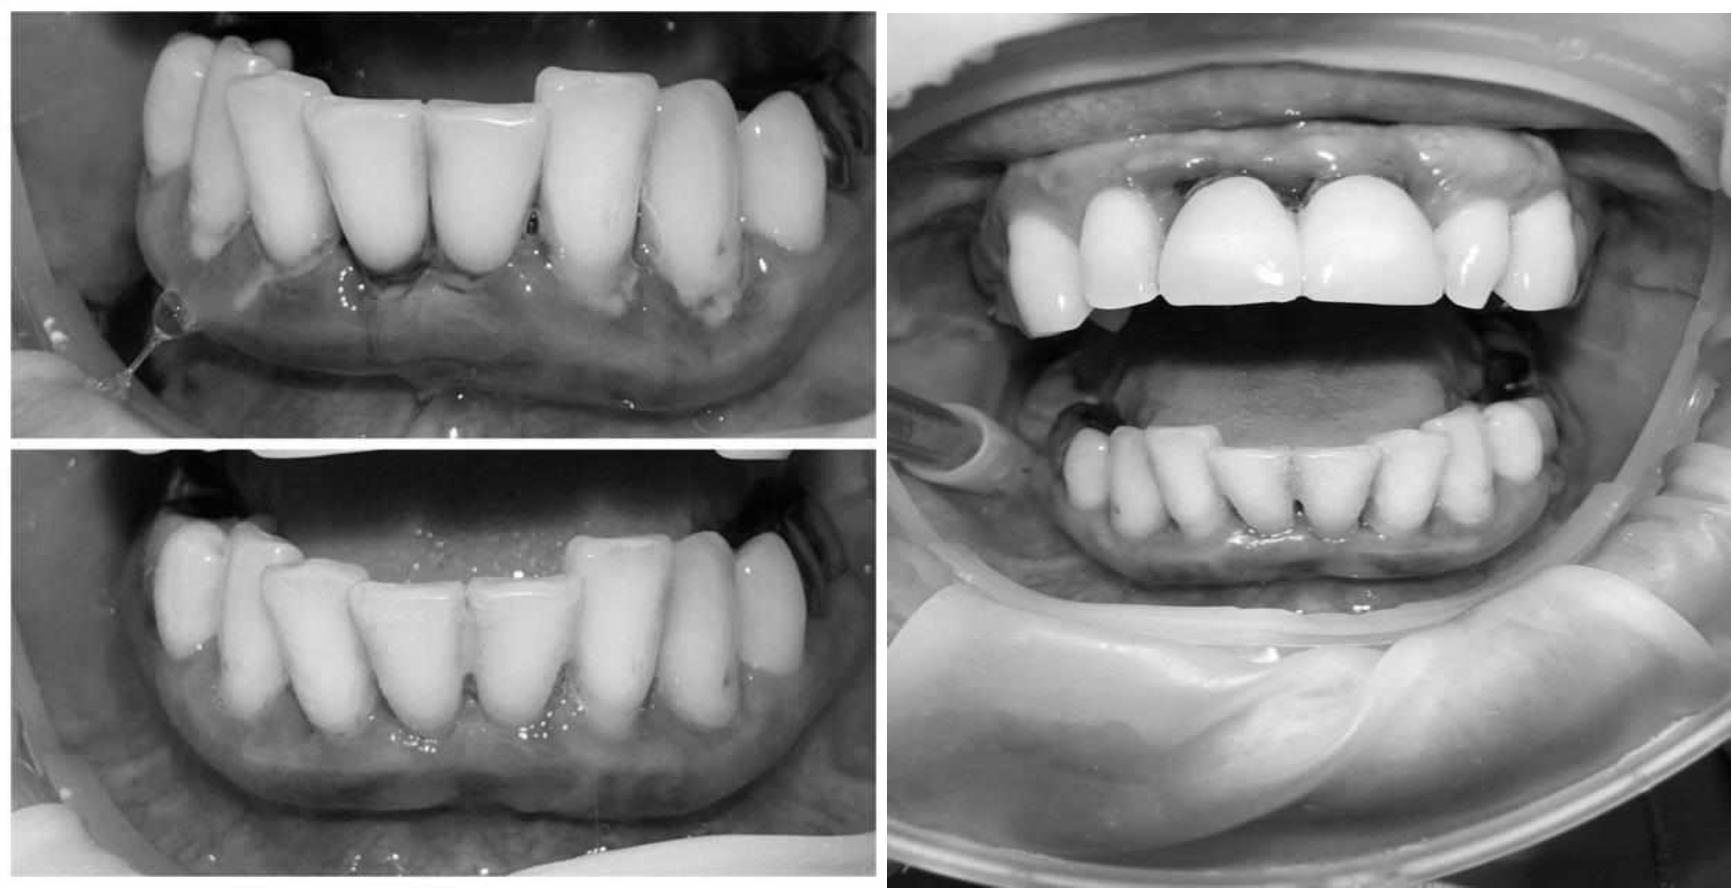

За пародонтологическим лечением обратилась женщина 61 года с жалобами на неприятный запах из полости рта, кровоточивость десен при чистке зубов, подвижность зубов, несостоятельность ортопедических конструкций.

Ранее у пародонтолога не наблюдалась. При осмотре выявлены: неудовлетворительная индивидуальная гигиена полости рта, пародонтальные карманы до 7 мм, обильная кровоточивость и гноетечение из пародонтальных карманов, подвижность зубов 4.2, 4.1, 3.1, 3.2 II степени, обильные над- и поддесневые зубные отложения (рис. 1). На ортопантомограме отмечается резорбция костной ткани до ½ длины корня, очаги остеопороза (рис. 2). Пациенту был поставлен диагноз хронический генерализованный пародонтит тяжелой степени тяжести. При осмотре была составлена пародонтограмма с использованием компьютерного зондирования (рис. 3).

Рис. 1. Внешний вид